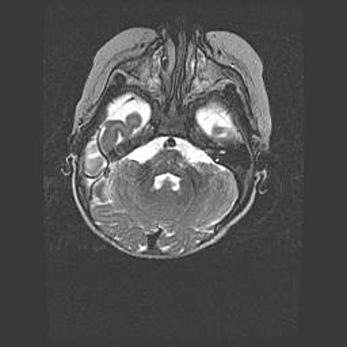

Подострая гематома правой гемисферы мозжечка.

Наружная гидроцефалия.

Возраст: 15 дней

Вес: 3100 г

Пол: женский

Окружность головы: 37 см

Срок гестации: 35-36 недель

При открытой наружной форме гидроцефалии у новорожденных расширяются и переполняются субарахноидные пространства.

Кровоизлияния в мозжечок имеют две клинико-анатомические формы: полушарные гематомы и кровоизлияния в червь.

К появлению этой патологии может привести: повреждения головного мозга, возникающие в результате асфиксии и гипоксии плода при беременности, или травмы во время родов. Редко гематома мозжечка может быть результатом первичной коагулопатии и сосудистой мальформации, диссеминированном внутрисосудистом свертывании, изоиммунной тромбоцитопении.